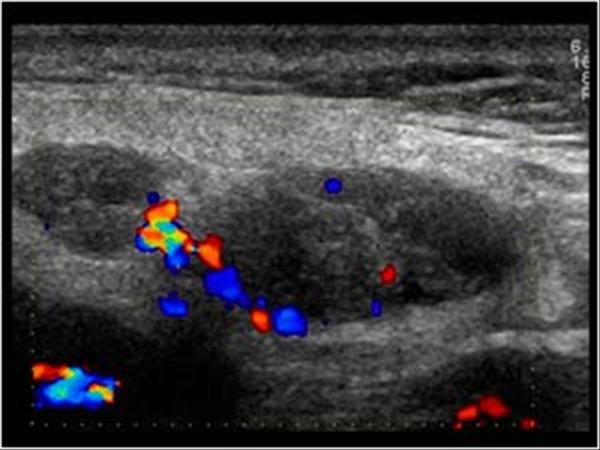

U tuyến nước bọt

» Thông tin: Nam giới – 64 tuổi.

» Lâm sàng: Khối vùng mang tai.

# U lympho tuyến nang (U Warthin) tuyến nước bọt mang tai.